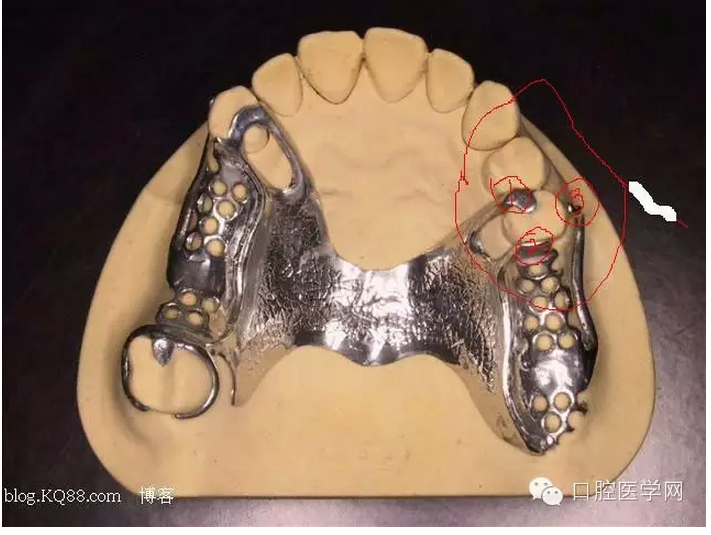

先注明一下:本文圖片部分來自李望松的支架設(shè)計圖譜收集u/210/archives/2008/25181.html,借圖表達一下,沒有別的目的,只是讓文章更生動些,李老師一直是我崇拜的偶像,只是近來很少見到他的文章,期待李老師的大作,言歸正傳——————修復大夫要精通支架設(shè)計,作為一個修復大夫,是第一個獲得患者牙體狀況的,所以說在哪放個合支拖,在哪放個卡換,至關(guān)重要,因為我們做的是個有創(chuàng)不可逆操作,既要兼顧牙周狀況,又要兼顧粘膜狀況,以及牙槽脊的情況,所以說當給患者做完檢查以后我們頭腦中就應該有一個大體支架了,以前,總是太依賴加工廠了,取完模剩下的好像都是交給了加工廠了,怎么設(shè)計,你看摸著辦吧,仿佛設(shè)計那是加工廠的事,可是做了幾回再加上自己的學習,經(jīng)驗,加工廠的設(shè)計總是不怎么樣,以前設(shè)計的方案仿佛根深蒂固,一直就認為那是正確的就那么設(shè)計,再加上以前看過支抗兄的一篇文章,也是深有感觸,一個不科學的設(shè)計方案,那樣就成了一個慢性拔牙器。看看幾幅圖片

看紅箭頭處為什么要空出一點距離?,看看自己加工廠設(shè)計的不管牙怎樣是不是都成了一個整體呢?對于愕板或者是

愕桿要離開齦緣4-6mm,以促進食物對牙齦的按摩沖刷作用,促進牙齦健康

前愕桿要離開至少6mm如下圖

愕板的后部(顫動線處)要與黏膜輕接觸,以防義齒行使功能時產(chǎn)生壓痛